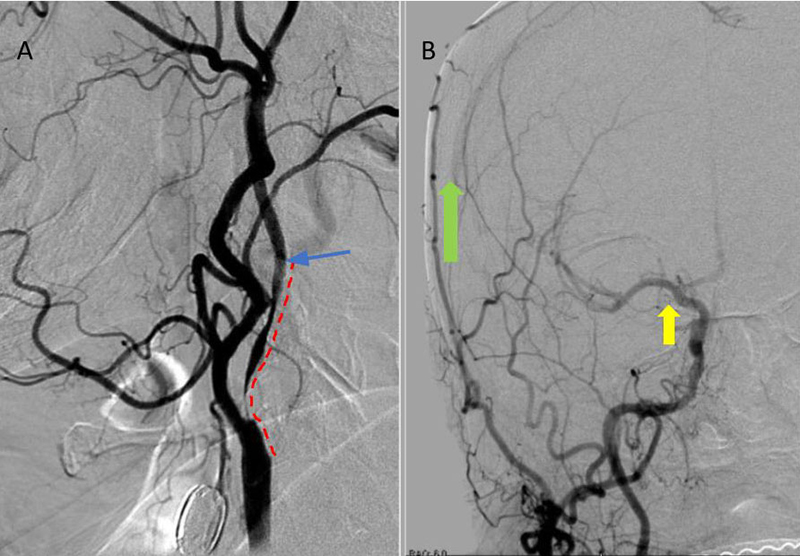

On admission, her initial CT scan was negative for stroke or hemorrhage, however a CTA demonstrated severe high grade 99% stenosis of the right Carotid bulb (ICA) with markedly diminished caliber of the cervical intracranial carotid artery secondary to calcified atherosclerosis without evidence of dissection (Figure 1).

Figure 1. A and B) CTA demonstrating severe ICA 99% stenosis (dotted) with flow-reduced diminution relative to the left ICA (red arrows) and distal plaque extension to C2 level.